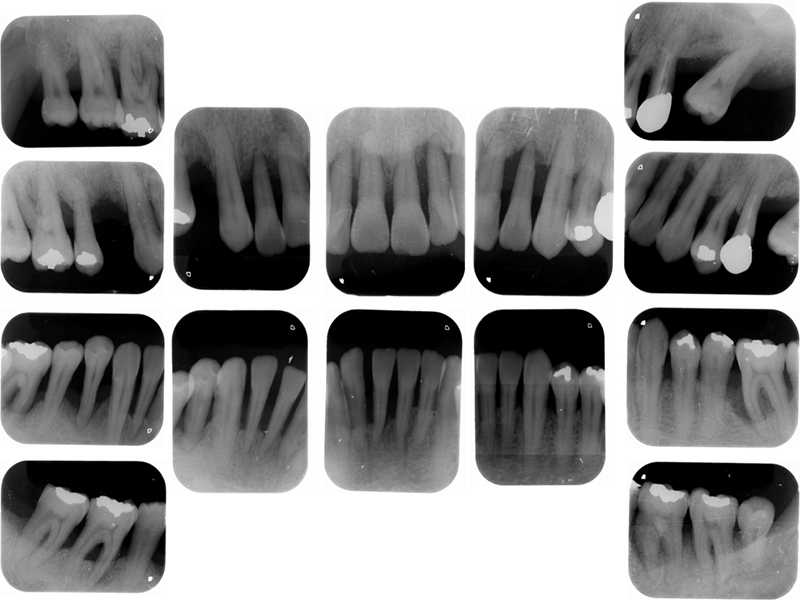

治療終了時